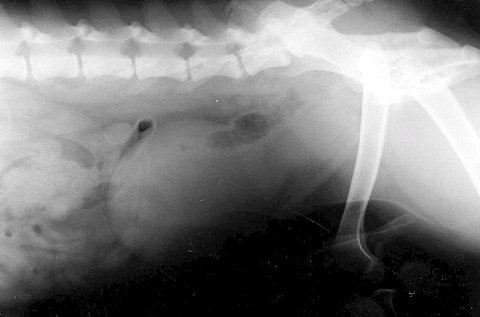

次は水腎症と言って、腎臓の周りに水(尿)が溜まってしまう病気です。

こうなってしまうと腎臓は元の形を留めていませんし、機能は完全に破綻しています。

幸いもう片側の腎臓は正常でしたので、悪い方は切除しました。

そしてこれが摘出した腎臓です。